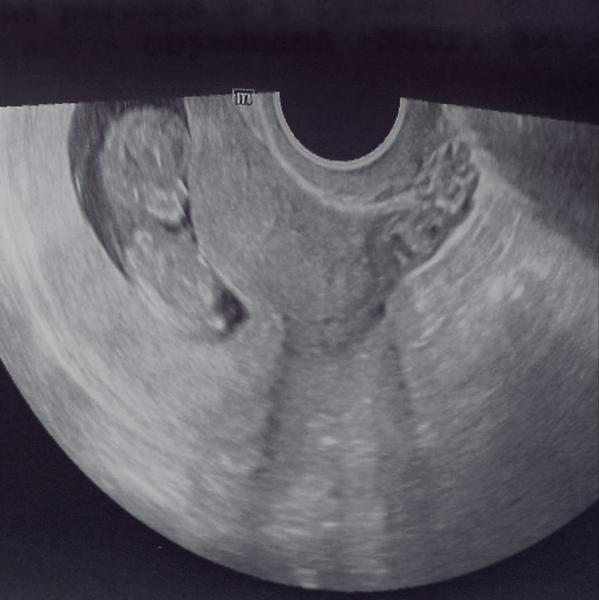

to je foto zo sona....záleží aký týždeň...hlavne zo začiatku dieťatko vyzerá ako mimozemšťan🙂toto ešte vyzerá fotka zo staršieho nie veľmi kvalitného sona ktorá aj dosť skresľuje...treba sa spýtať lekára ktorý s tým robí a nie žien z MK ...podľa tohto to ešte vyzerá tehotenstvo v začiatkoch, takže pochybujem že lekár vie určiť už pohlavie....

z tejto fotky to dobre nevidno ale dieťatko má pokrčené nôžky pri brušku, preto sa ti môže zdať veľká hlavička.....gynekológ ti neukazoval čo vidí? kde má dieťatko srdiečko, nožičky, rúčky? nemeral ho? neboj sa, na budúce bude aj lepšia fotka, ak sa dá pýtaj si 3D alebo 4D, naozaj to stojí za to.....ale ak lekár tvrdí že je bábo ok, tak aj je.....ak by sa mu niečo nezdalo, už by ťa posielal na ďaľšie vyšetrenia.....